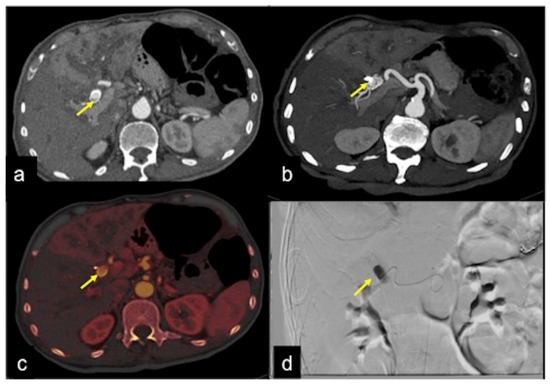

| Haemobilia (Figure 32) | Melaena, haematemesis, biliary colic, jaundice, or massive bleeding in a patient with a history of blunt or iatrogenic abdominal trauma. | Presence of blood in the gallbladder and biliary tree. |

| Pancreatic Haemorrhage | Intermittent epigastric pain in the abdomen, gastrointestinal bleeding (melaena, haematemesis, haematochezia) and raised serum amylase. | Pseudoaneurysm or pseudocyst with signs of active bleeding, associated with the finding of hyperdense material in the pancreatic ducts. |